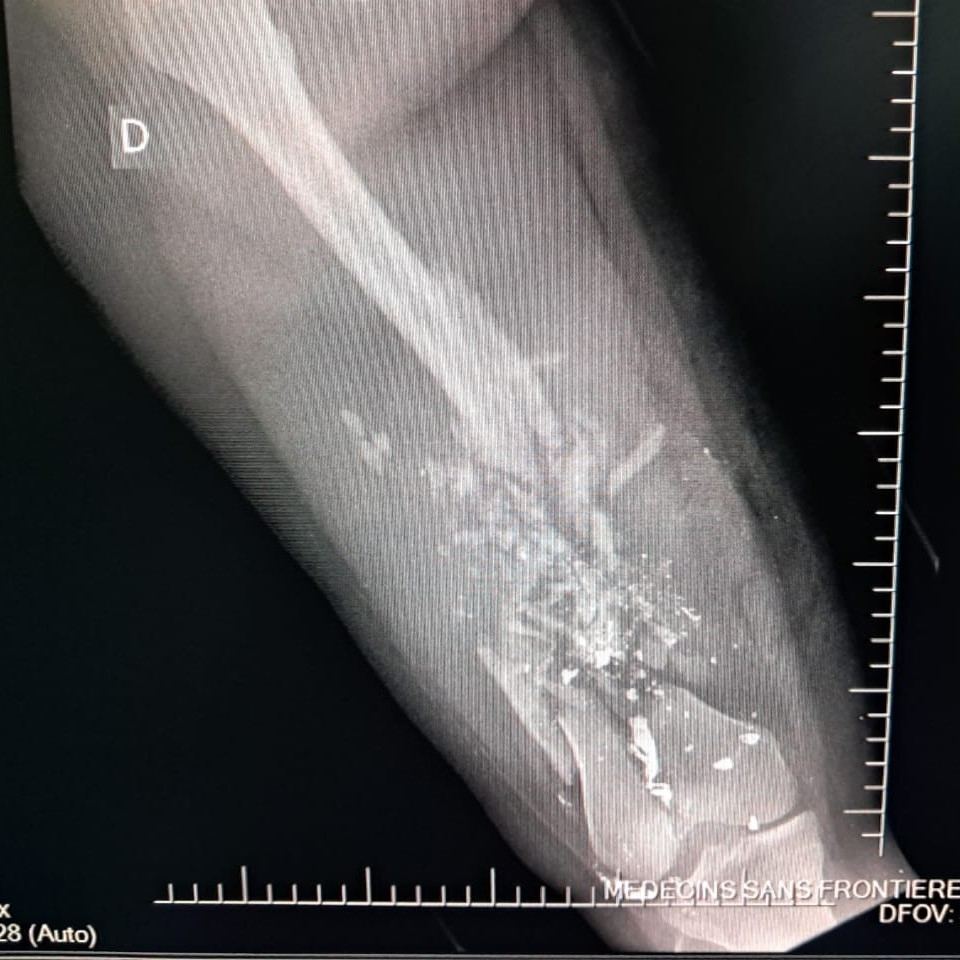

Between January and June 2025, MSF teams assisted 2,600 survivors of sexual violence, admitted 13,300 patients to emergency rooms and treated 2,267 victims of violence. Among these, 26 percent were minors, compared to 11 percent in 2024. Most minors were under the age of 15, and one third were girls. Thirty percent of all minors admitted for violence-related injuries suffered gunshot wounds.

On September 20, 17 wounded people were treated at the MSF hospital in Drouillard following a drone attack carried out the same day in the Cité Soleil neighbourhood. Among these patients, were two men who were already dead on arrival, another man who died while being transferred, ten women—one of whom died en route to MSF’s trauma hospital in Tabarre—and three children who tragically did not survive their injuries. Two more women injured in this attack died at the nearby Isaïe Jeanty maternity hospital, where MSF is also working.